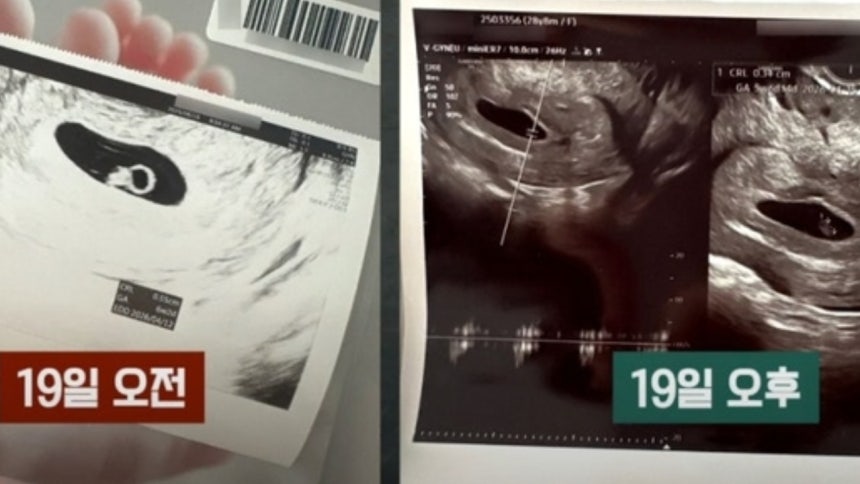

지난 19일, 첫아이를 품고 있던 한 부부가 설레는 마음으로 정기 검진을 위해 부산의 한 산부인과를 찾았습니다. 👣 그러나 행복한 기대는 곧 하늘이 무너지는 듯한 충격으로 변했습니다. 담당 의사는 초음파 검진 후 "아기의 심장이 뛰지 않는다"는 믿기 어려운 진단을 내렸습니다. 절망에 빠진 부부에게 의사는 "다음 임신을 위해 오늘 아기집을 제거하는 것이 좋다"며 덤덤하게 시술을 권유했습니다. 부인은 오열했고, 남편은 억장이 무너지는 고통 속에서도 "내일 다시 오겠다"는 말을 겨우 남긴 채 병원을 나올 수밖에 없었습니다.

그러나 남편은 마지막 희망의 끈을 놓지 않았습니다. 혹시라도 모를 마음에 부부의 손을 잡고 다른 산부인과 병원을 찾았습니다. 🏥 그리고 그곳에서 기적과도 같은 이야기를 들었습니다. 다른 병원의 의사는 "심장 소리가 약하다"면서도 "아기에게 좋은 징조는 아니지만 일단 며칠 두고 보자"는 신중하고 희망적인 태도를 보였습니다. 이 말 한마디는 부부에게 다시금 살아갈 용기와 희망을 불어넣어 주었습니다.